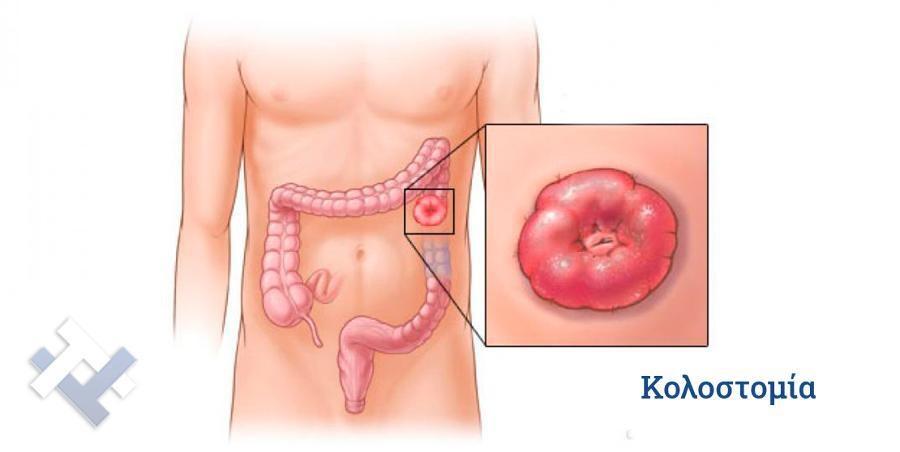

Ο Γενικός Χειρουργός Λιάγκος Γεώργιος MD PhD εκτελεί τις επεμβάσεις Λαπαροσκοπικά, Ενδοσκοπικά, Ανοιχτά Ελάχιστα Επεμβατικά και με Laser. Η θεραπεία εξατομικεύεται σε κάθε ασθενή ανάλογα με τις ανάγκες του. Αναλαμβάνει περιπτώσεις όπως κήλες και κοιλιοκήλες (αντιμετώπιση βουβωνοκήλης, αντιμετώπιση ομφαλοκήλης, θεραπεία επιγαστρικής κήλης, κήλη των αθλητών (Σύνδρομο κοιλιακών προσαγωγών), αντιμετώπιση μετεγχειρητικής κήλης, θεραπεία Μηροκήλης), πέτρες στη χοληδόχο κύστη, λαπαροσκοπική χολοκυστεκτομή, αντιμετώπιση Κύστη Κόκκυγος με λέιζερ (laser), παθήσεις πρωκτού, χειρουργική laser σύγχρονων κυκλικών ινών (αιμορροΐδες αντιμετώπιση, θεραπεία αιμορροϊδων με laser (LHP), αφαίρεση αιμορροΐδων με υπερήχους (HALL-RAR), χωρίς Χειρουργείο με ελαστικούς δακτυλίους (Τεχνική BARON-RBL), θεραπεία ραγάδας πρωκτού (Ραγάδα δακτυλίου), θεραπεία περιεδρικού συριγγίου, θεραπεία περιεδρικού αποστήματος, κονδυλώματα πρωκτού Θεραπεία, δερματικό ράκος (Skin tag) εκτομή, αντιμετώπιση Kνησμού, καρκίνος πρωκτού θεραπεία), παθήσεις Δέρματος, χειρουργική με laser CO2, αφαίρεση μορφωμάτων δέρματος - βιοψίες, αφαίρεση ελιάς (Σπίλου), σμηγματογόνος κύστης θεραπεία, αφαίρεση λιπώματος, είσφρυση όνυχος χειρουργείο, καρκίνος δέρματος θεραπεία, οξεία σκωληκοειδίτιδα, παθήσεις Λεπτού και Παχέος Εντέρου, ειλεός λεπτού εντέρου, εκκολπωμάτωση (Εκκολπωματίτιδα) σιγμοειδούς, καρκίνος παχέος εντέου, κολοστομίες, port χημειοθεραπείας κ.α. εξυπηρετώντας Παγκράτι και γύρω περιοχές.